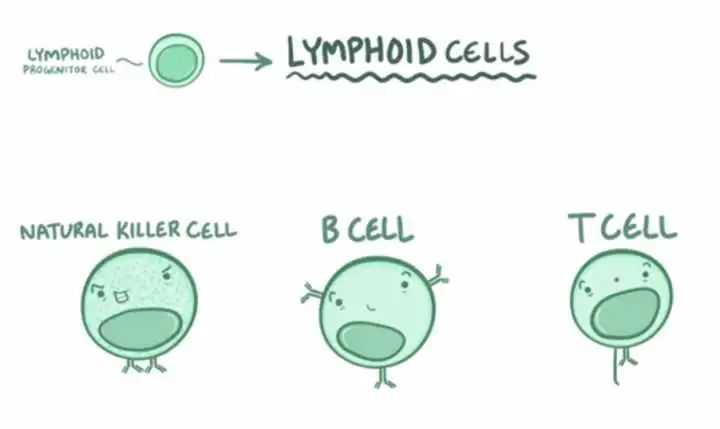

再拿打的流感疫苗来说,往身体里注射了灭活的流感病毒,我们的固有免疫系统当然是无法识别他,通过发烧也消灭不了它,病毒还是存在于血液和淋巴液里,于是淋巴结里的巨噬细胞和血液里的单核细胞就要想办法搬救兵了,那就是免疫细胞的三大将——T细胞、B细胞、NK细胞。

从左到右:NK细胞、B细胞、T细胞

T细胞就像医院门口检查健康码的保安大叔,面对汹涌的排队大军,它要做到忙而不乱,快速独立判断对方是敌是友,毕竟很多人拿着健康码截屏都能混入,病毒细菌有时候更加狡猾,只有经过长时间艰苦的训练,T细胞才能独当一面。

B细胞就像奇门遁甲的忍者,当遇到无法杀灭的病毒时,它们会第一时间使出“影分身”,分裂出大量B细胞一起制造数以万计的抗体,就像手里剑一样往病毒身上发射,杀死病毒的同时,也研发出了可用于对付他们的“专门武器”,未来一旦不幸再次感染,这条生产线就会快速响应,把病毒扼杀在摇篮里。

NK细胞(自然杀伤细胞)就像个毫无感情的杀手,它可以快速标记非自身细胞,只要发现病毒或者肿瘤细胞不是自身的,就二话不说把它们杀灭。但冲动的性格,也让它们时常“好心办坏事”,过敏反应和自身免疫性疾病的发生大多都有它的身影。

这三种免疫细胞,一定程度可以反映我们身体的免疫情况。当他们的数量下降,就表示身体免疫功能有点减退了;当NK细胞过高,又能反映免疫过于亢进。